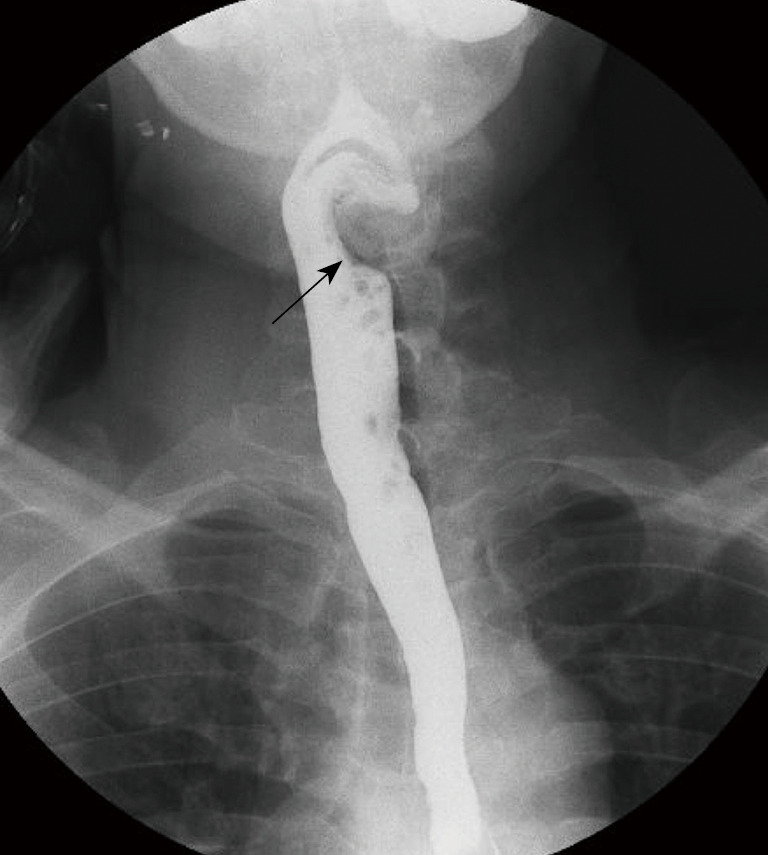

Case description: We report the case of a 51-year-old man, with no specific past medical history, who has been complaining of a 3-months pain in the left side of the tongue base with sensation of a lump in the throat and dysphagia. Computed tomography scan confirmed DISH between C4 and C7. Barium swallow fluoroscopy demonstrated indentation of the esophagus only at the level of C4-C5, which guided the surgical management that focused on resecting only the major osteophytes at the level of C4-C5, avoiding extensive approach with its subsequent possible complications, and enabling satisfactory clinical and radiological outcomes.

Conclusions: The current case thoroughly illustrated the diagnosis and surgical management in the presence of dysphagia from DISH. Through an anterior pre-vascular approach complete resection of the major osteophytes could be done. Barium swallow fluoroscopy showed very high interest in dynamically demonstrating the main level causing the dysphagia symptoms and also confirming satisfactory esophagus decompression and release after surgery.